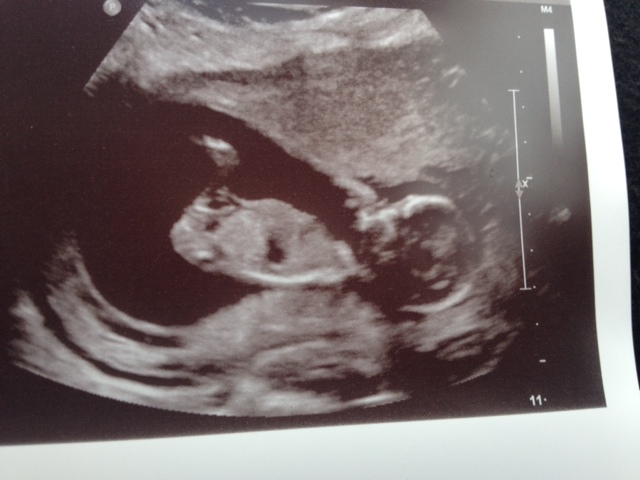

UPDATED-scroll down! Hi! I had my nt scan today but baby was measuring too big so they couldn't do the test. I did get 3 photos though. Thanks!Attachment 18197Attachment 18198Attachment 18199